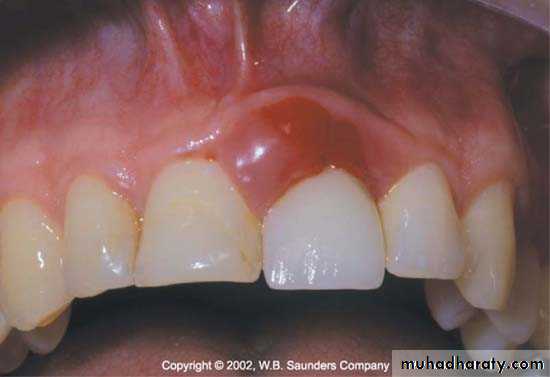

Contour of restoration

• Over contoured restoration:• accumulate plaque& prevent self-cleaning by tongue, lips & cheek .

• Improperly located proximal contact that is located more apically with inadequate gingival embrasure spaces associated with papillary inflammation.

• Restorations contour is extremely important to the maintain periodontal health.• Ideal contour provides

The most frequent cause of overcontoured restorations is inadequate tooth preparation by the dentist, which forces the technician to produce a bulky restoration to provide room for the restorative material.

Contour of artificial crown or bridge or restoration should be cleansable so as to decrease plaque retention & gingival inflammation .